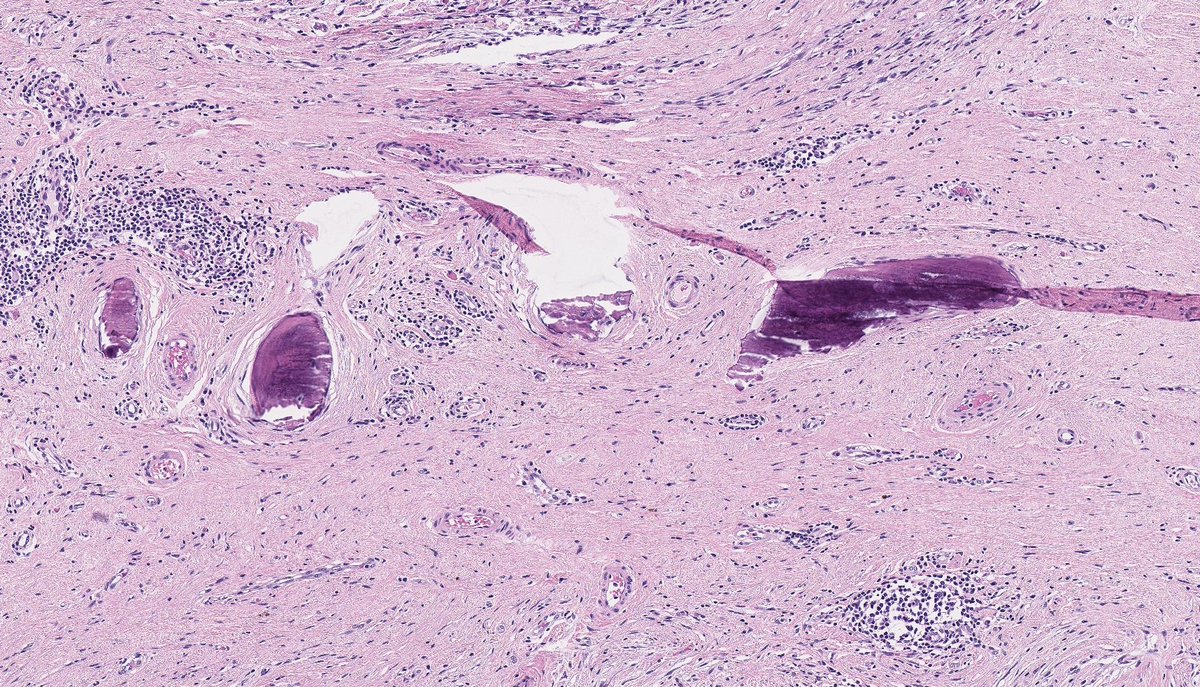

DEDIFFERENTIATED LIPOSARCOMA (with meningothelial-like whorls and metaplastic bone formation). (FISH: + MDM2 amplification.) PMID: 9839165, 21317707.